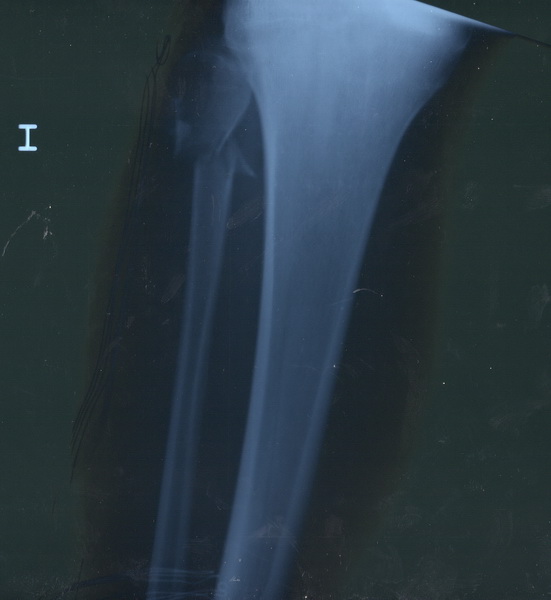

Al llegar al hospital de Riotinto, se le practica exploración y estudio radiológico, se confirma nuestro diagnóstico. Al no haber desalineación de fragmentos óseos, se proceden a inmovilizar la extremidad con férula posterior para tener acceso a la herida, poder realizar curas locales y retirada paulatina de drenaje.